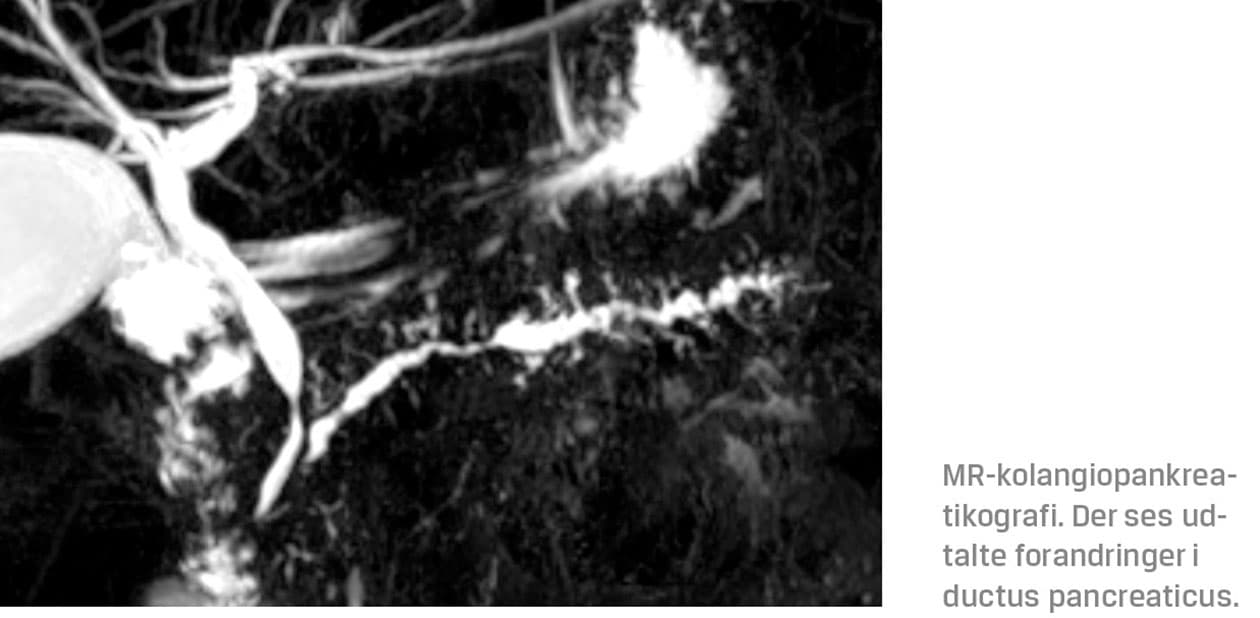

Lignende fund blev rapporteret i et fransk studie med 200 patienter med HP, hvor medianalderen for debut af pankreatitissymptomer var ti år og 23 år for udvikling af KP [4]. Patienterne havde AP i 69% (n = 135) af tilfældene, forkalkninger i pancreas i 61% (n = 113 ud af 186), og ductusforandringer i 63% (n = 117 ud af 185). Medianalderen for diagnosticering af HP i den franske kohorte var 27 år.